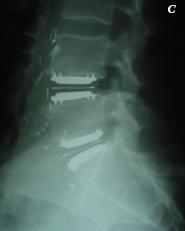

- A- posnetek z magnetnoresonancnim tomografom. Degeneracija zadnjih dveh diskov je ocitna.

- B- rentgenski posnetek, Ledvena hrbtenica 57-letnega moškega v stranski projekciji:

- C- rentgenski posnetek po vstavitvi dveh diskalnih endoprotez, s katerima smo nadomestili okvarjeni medvretencni plošcici